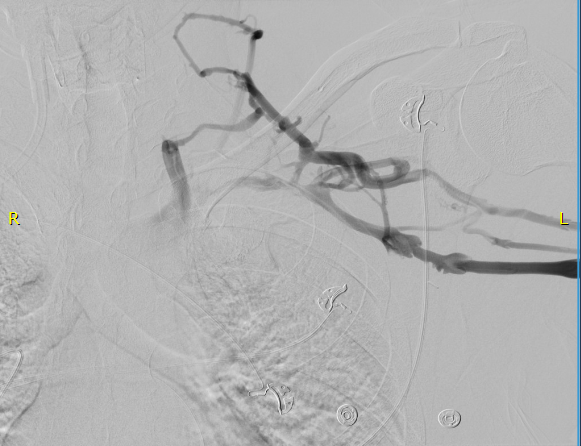

The patient did well, recovering much of his range of motion quickly with the help of physical therapy. He was taken to the angio suite and underwent venography shown below. There is an occlusion of the subclavian with outflow via collateral veins. Not seeing collaterals is as important as seeing a good angiographic result. pre intervention

Venoplasty was done to 8mm -I try not be overly aggressive here, just to break the strictures that caused the balloon to have a waist in two sections. The final result is below, with the absence of the venous collaterals. If they were still present despite an angiographically satisfactory result, I would perform IVUS to see what the problem was. In no circumstances would I place a stent at this juncture -my plan is to keep the patient on anticoagulation for 3 more months.

post intervention